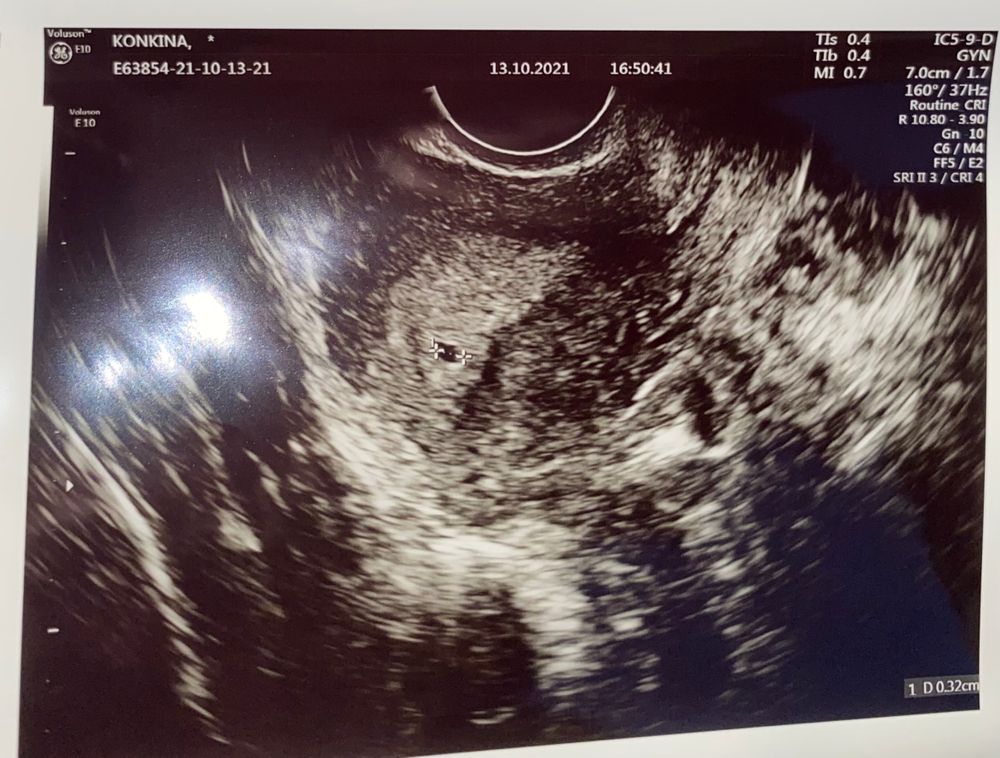

Приветики ))) Писала про слабую динамику тестов и про то что не удваивается хгч, что думала что опять бхб , так вот кд так и не начинаются, задержка 4 дня тесты не делала, хгч не сдавала в итоге сходила на узи вчера и нашли пя 3мм, что соответствует сроку 2-3 недели, и сказали что хгч это тоже все индивидуально ❤️ Сказали, что нужно надеятся на лучшее и смотреть динамику и через 10 дней повторное узи :)